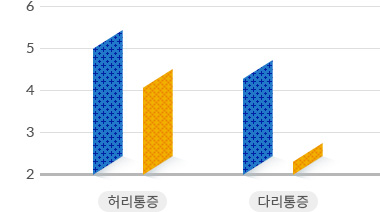

척추관협착증 수술 vs 비수술 치료 통증 감소 효과 비교

수술치료

수술치료

비수술치료

비수술치료